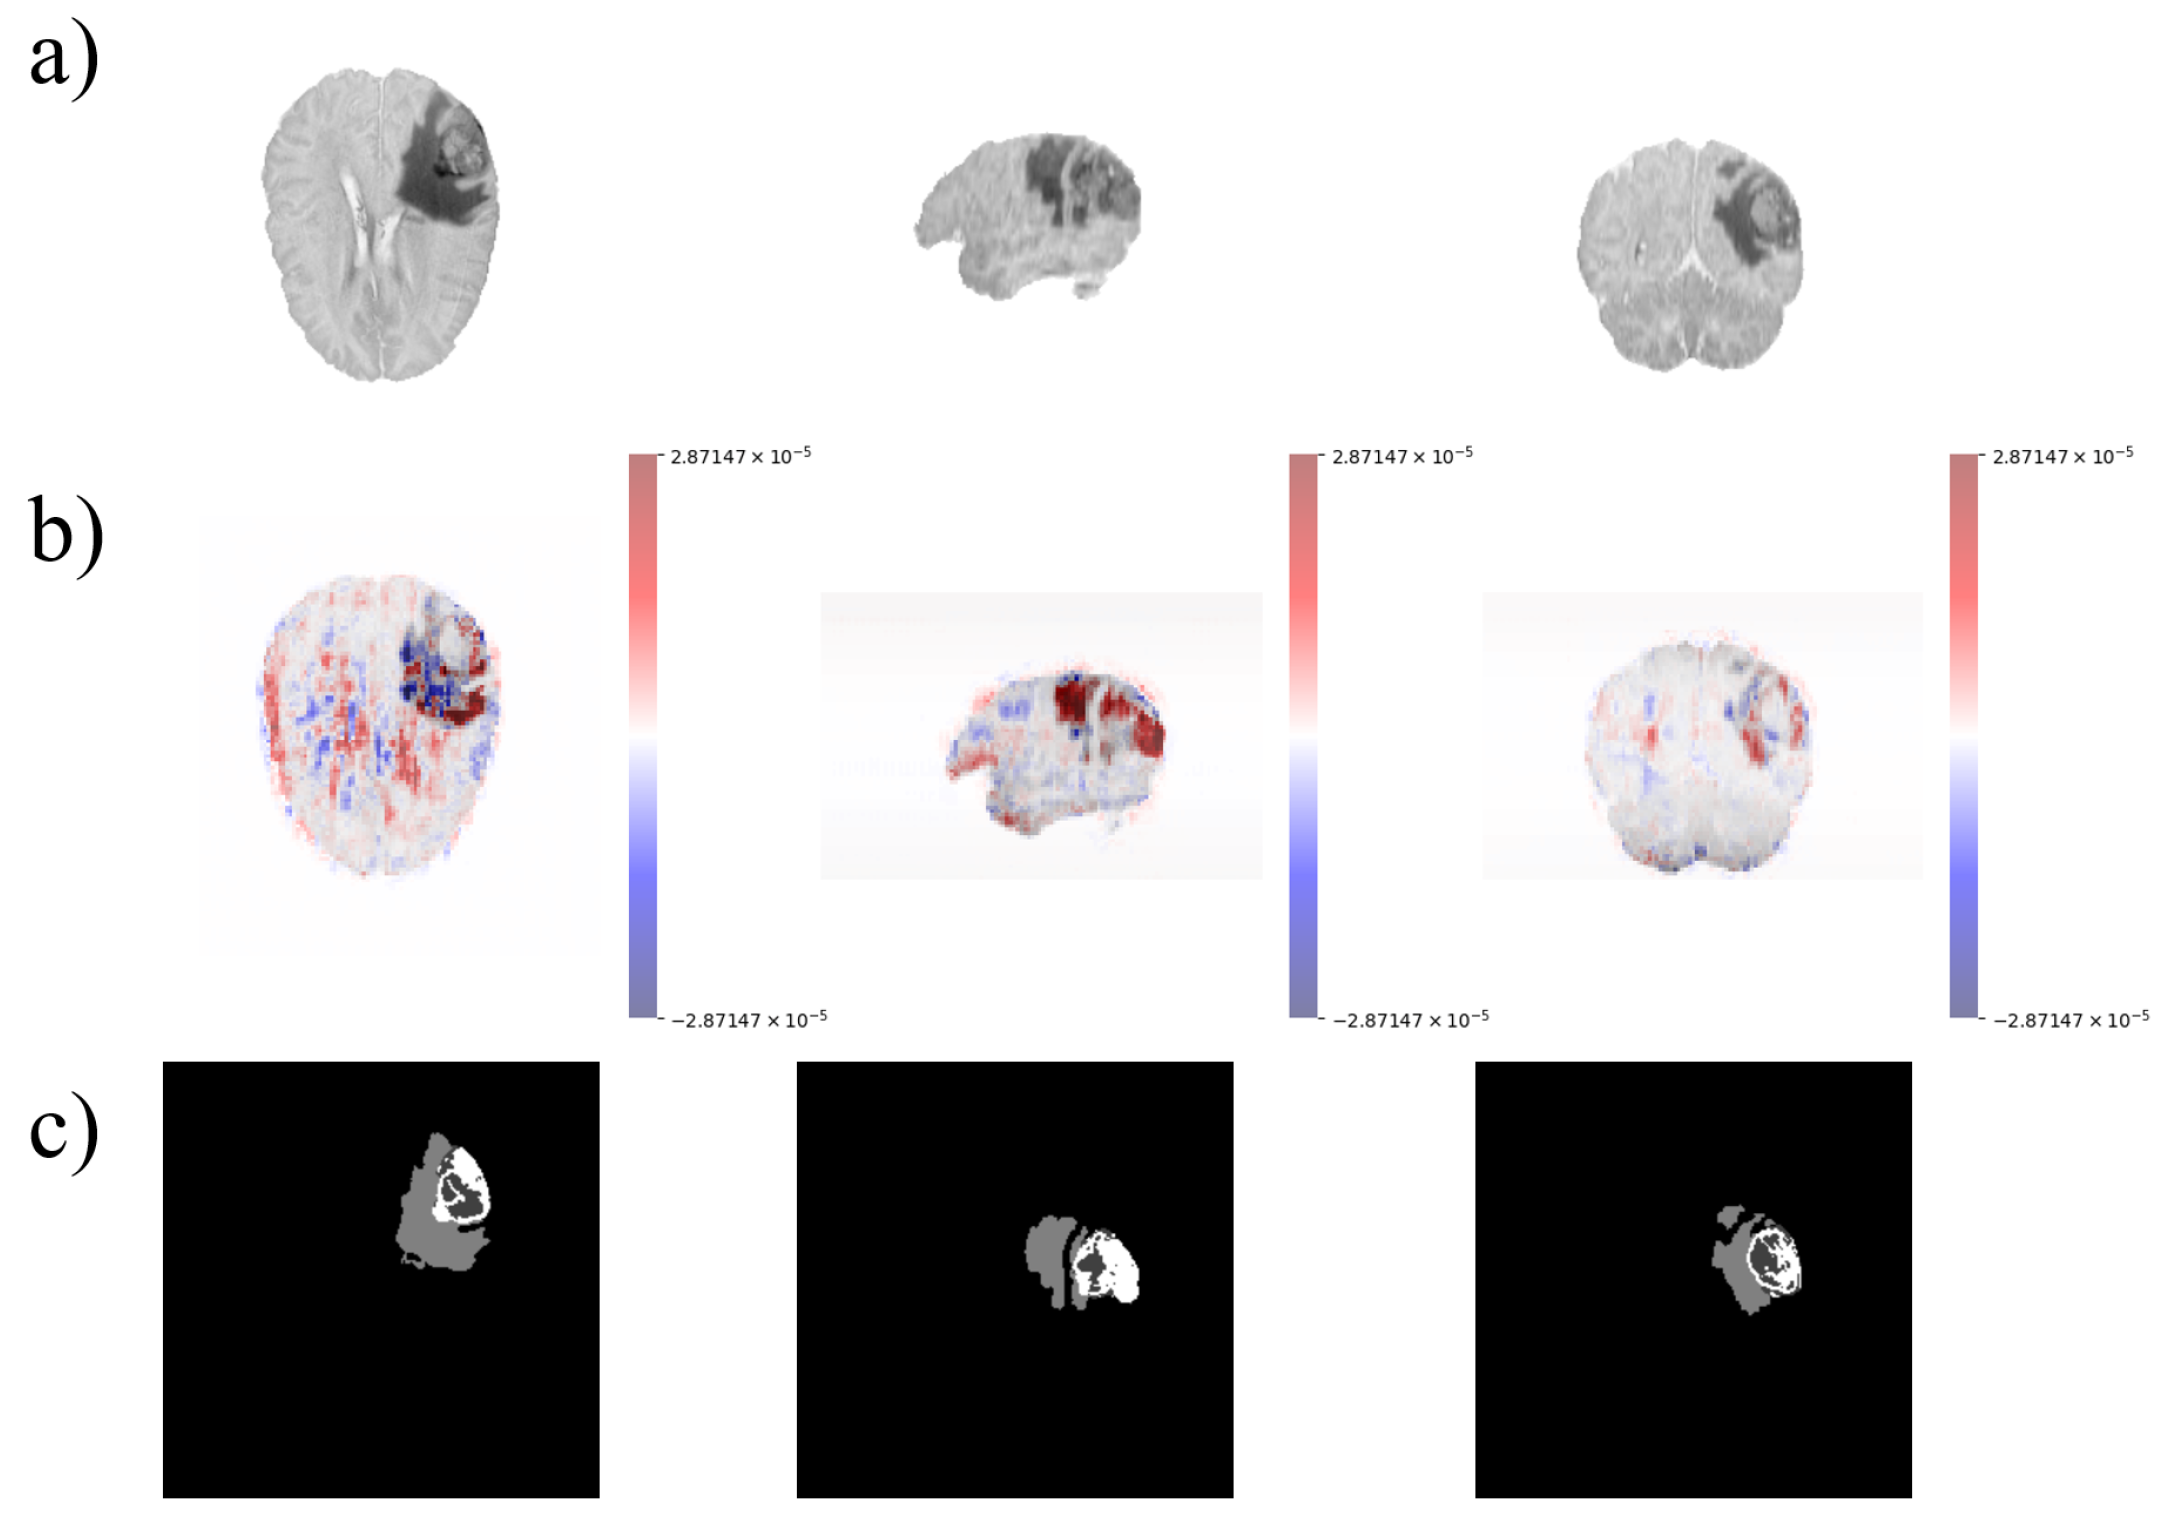

2.1. Data Pre-Processing

2.3. Explainability